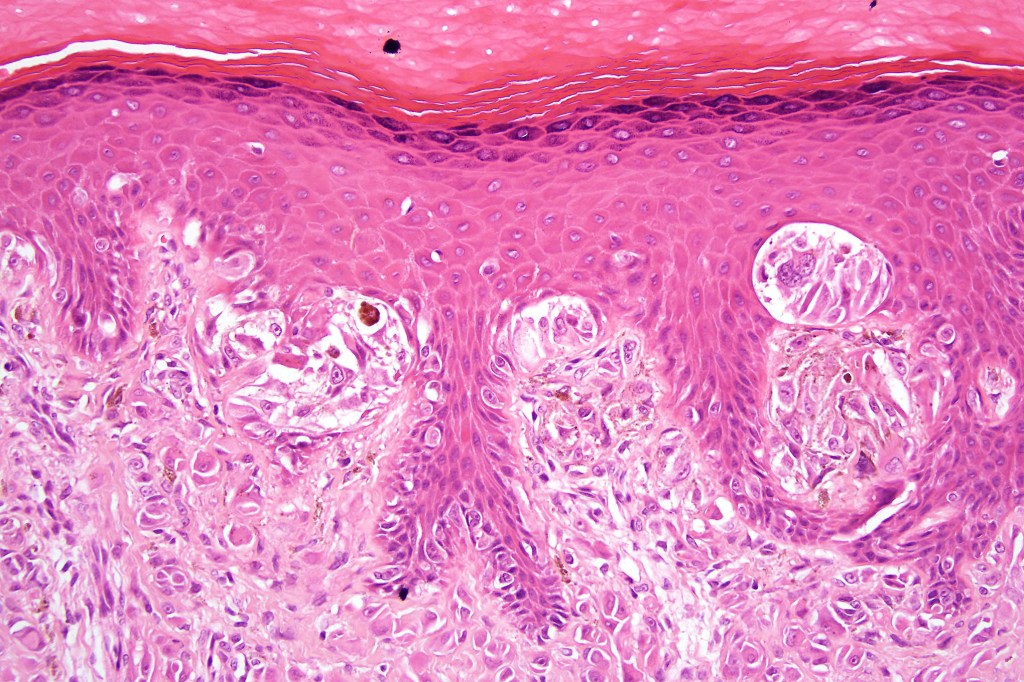

•Hyperkeratosis & acanthosis, sometimes very marked

•Pseudoepitheliomatous hyperplasia

•Superficial vascular ectasia very frequently present

•Kamino bodies (often multiple) are a characteristic feature